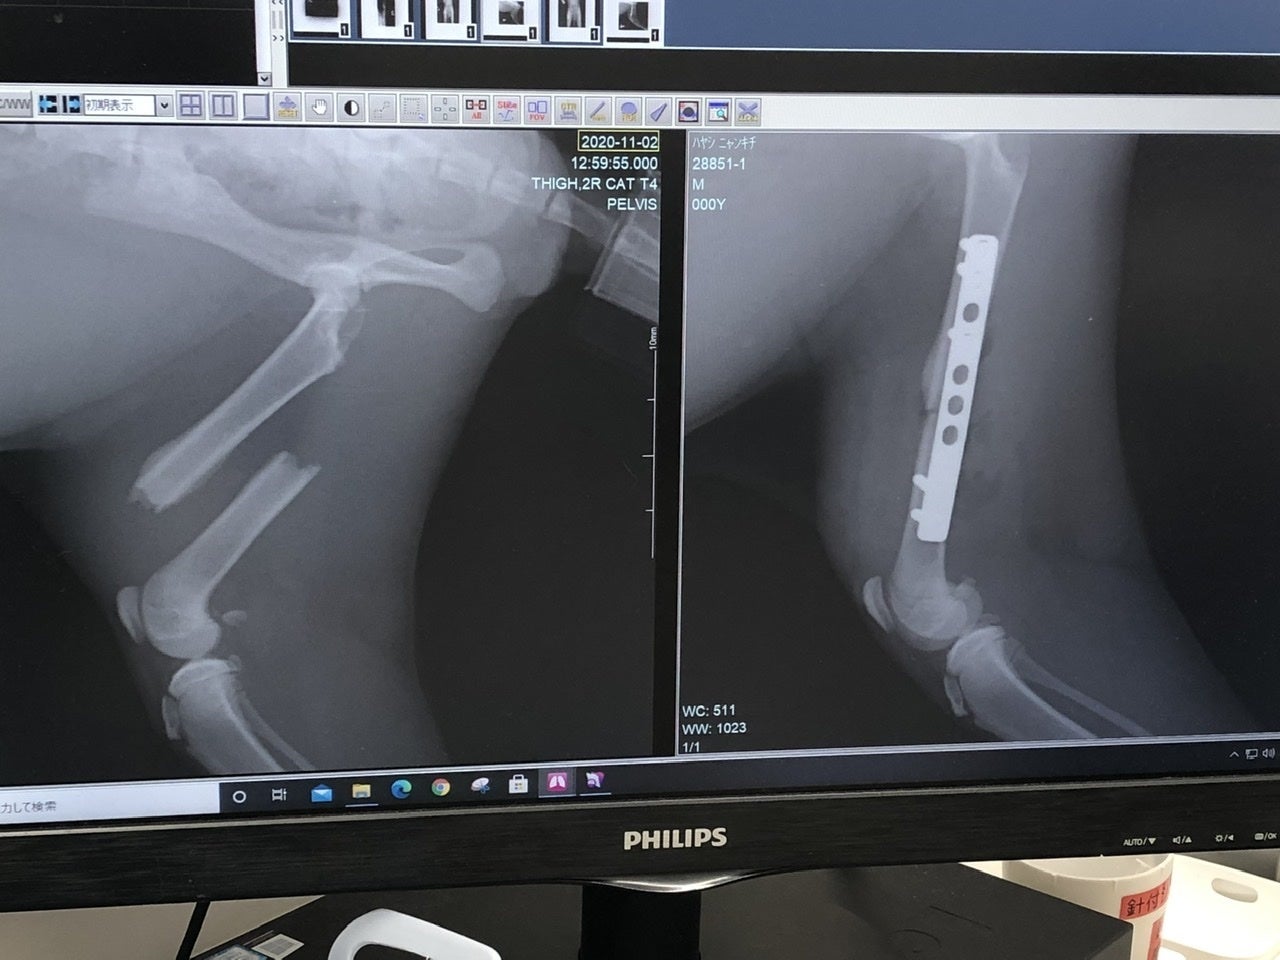

「右後ろ大腿骨(付根)」は肉を剥がして奥まで入った骨を戻し、固定の金具をつけます。

次に金具を入れて固定した画像。The 骨折画像と比べると、本当に綺麗に固定されていました。でもまあ、よくこんな折れた状態で店まで、歩いてきたなと。